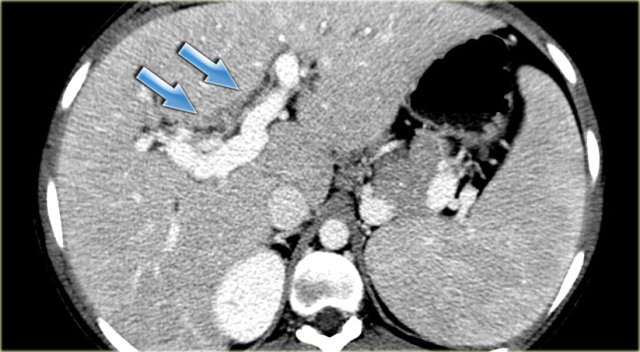

Study the image on the left.

Then continue reading.

The findings are:

- Medullary sponge kidney with stone formation (red arrow)

- Mild bile duct dilatation (blue arrow)

- Round hypoattenuating mass in the right liver lobe

The mass in the right lobe of the liver turned out to be an abscess.

Remember that liver abscesses in the early phase can look quite solid.

In the differential diagnosis we would also have to include a neoplasm, because patients with Caroli disease have an increased risk of developing a cholangiocarcinoma.